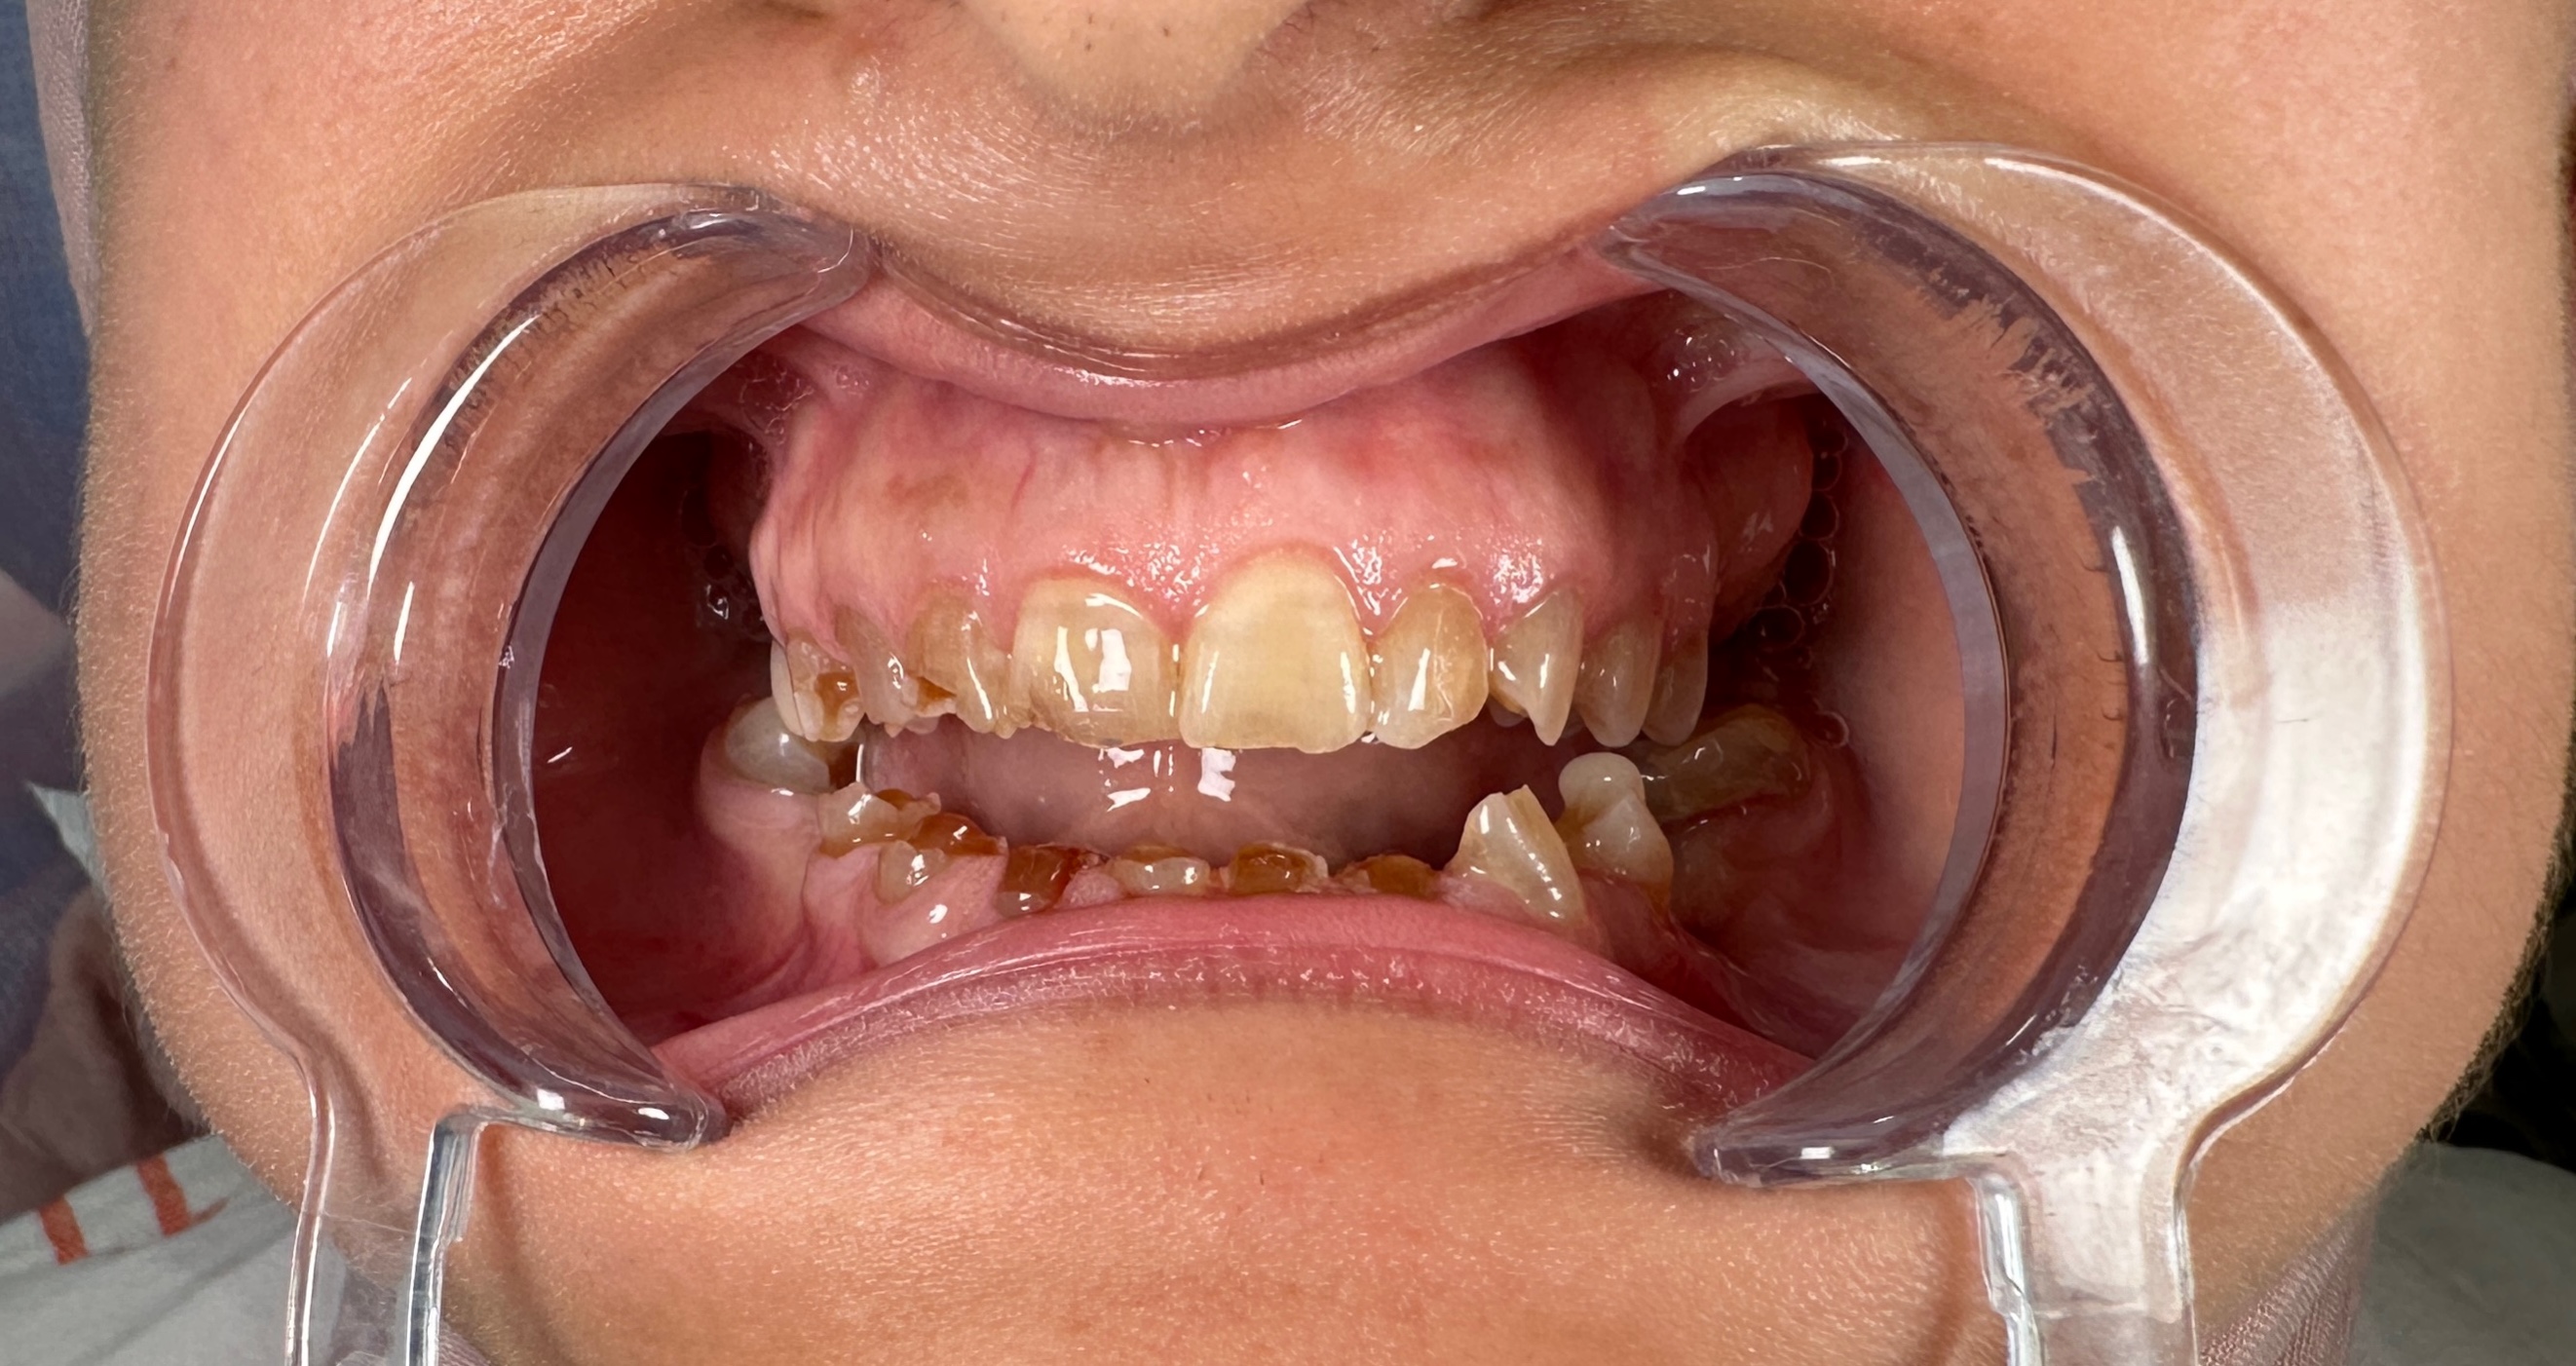

Öncesi Sonrası

Öncesi

Sonrası